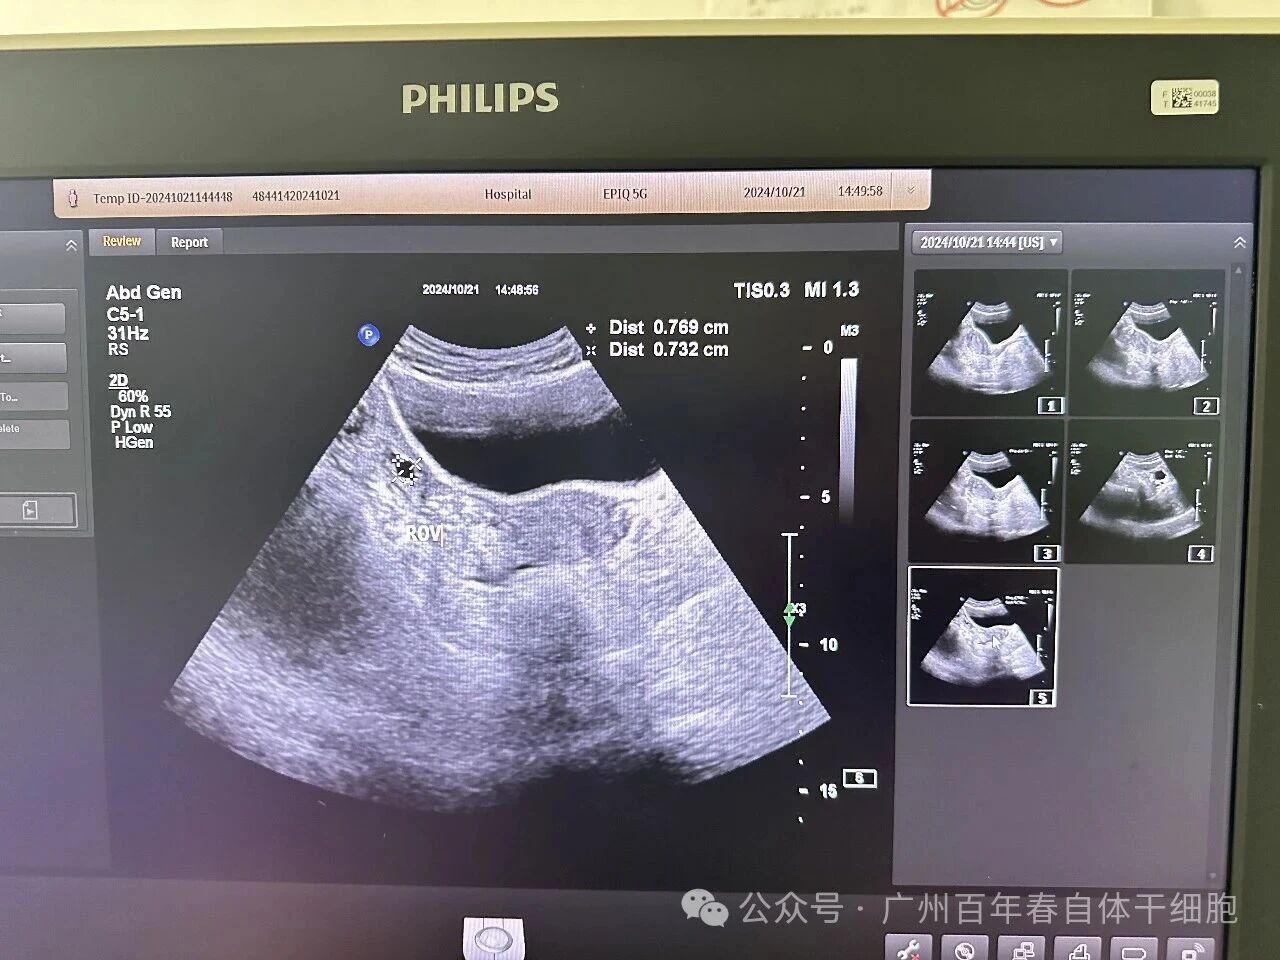

△保健后45天B超复查

案例2:47岁的杨女士卵巢功能衰竭、月经不规律、连续9次流产,因想要小孩近两年服用激素类药物维持排卵功能,但停药后月经即停,更让她陷入“药物依赖-功能衰退”的恶性循环。B超检查仅见受压的窦性卵泡,其卵巢功能已如“枯树”,难以自然恢复。